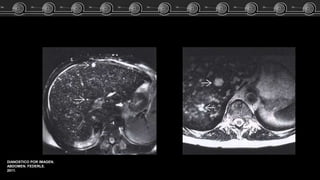

• T1:

Isointensos o lig. hipointenso.

Cicatriz central: Hipointensa.

RM

• T2:

Hiperintensa a isointensa

Cicatriz central: Hiperintensa.

• T1 + C:

Hiperintensa homogénea.

Cicatriz hipointensa.

• T1: Isointensos olig. hipointenso. Cicatriz central: Hipointensa. RM • T2: Hiperintensa a isointensa Cicatriz central: Hiperintensa. • T1 + C: Hiperintensa homogénea. Cicatriz hipointensa. HiperplasiaNódular Focal